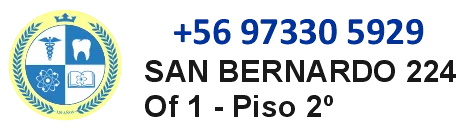

En este caso se trató de un paciente de 13 años con alteración de erupción y caninos permanentes retenidos en posición profunda. El análisis clínico y radiográfico permitió confirmar la necesidad de manejo ortodóntico-quirúrgico, junto con una estrategia secuencial para recuperar espacio y mejorar la predictibilidad del tratamiento.

Primera fase: expansión y ortodoncia interceptiva

La primera etapa comenzó durante el crecimiento, con expansión mediante quad-helix y ortodoncia interceptiva. Esta fase no buscó “apurar” el tratamiento, sino desarrollar mejor el maxilar, recuperar espacio y preparar condiciones biomecánicas más favorables para el descenso futuro del canino retenido.